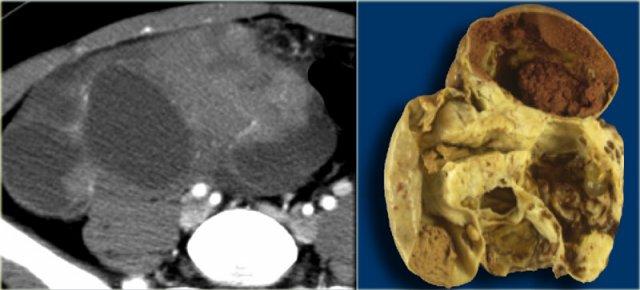

Siêu âm cho thấy một khối đặc-nang phức tạp ở buồng trứng trái, và một khối đặc-nang phức tạp khác có kích thước rất lớn ở nửa chậu hông phải.

CT của cùng bệnh nhân cho thấy một khối đặc-nang phức tạp với các vách dày có ngấm thuốc ở buồng trứng phải.

Các đặc điểm này rất nghi ngờ cho một u nang buồng trứng ác tính.

Ngoài ra còn có hạch bạch huyết to hai bên (mũi tên).

Kết quả giải phẫu bệnh cho thấy đây là ung thư biểu mô tuyến nang thanh dịch buồng trứng.

Đây là loại ung thư buồng trứng thường gặp nhất.